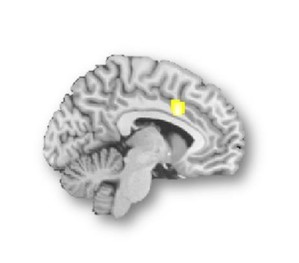

▲사진="대화 집중 못 하는 '스마트폰 중독'…알고보니 뇌에 문제".뇌기능 MRI 영상에서 갈등의 탐지와 조절에 관련된 뇌 속 '배외측전전두피질'과 '전대상피질'에서 상대적으로 저하된 뇌활성화가 관측된 모습. [제공/서울성모병원 정신 ...